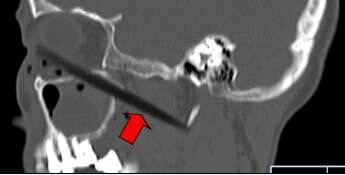

CT顯示筷子還插在腦部

取出的斷筷有9厘米

上周三,62歲的依姆林瓊(化名)在南平家中,有人在揮舞筷子時,將筷子從她右眼眶插入,鼻孔瞬間出血。家人心急,用老虎鉗將筷子外端夾斷,剩下半截筷子嵌在頭面部,之后將其緊急送到福建醫(yī)科大學(xué)附一醫(yī)院。經(jīng)過1個多小時的緊急手術(shù),9厘米長的斷筷被取出,由于筷子未插中眼球,患者眼睛未受影響。附一醫(yī)院耳鼻喉科副主任醫(yī)師張暉萍提醒,千萬不可自行強拔已插入體內(nèi)的物體。傷者被送到附一醫(yī)院時,醫(yī)生幾乎都看不到筷子了。在醫(yī)生的詢問下,家屬這才說,當時,他們一心急,用老虎鉗將筷子外端夾斷。這下棘手了。若筷子是完整的還容易拔出,這下完全埋在眼眶下,可怎么取出?影像學(xué)檢查顯示,筷子就靠近視神經(jīng)管、頜內(nèi)血管分支,末端位于頸部大動脈的前方。手術(shù)稍有不慎,就可能大出血。為了取出斷筷,附一醫(yī)院耳鼻喉科、頜面外科、眼科、影像科馬上聯(lián)合會診,擬定了三套手術(shù)方案。第一方案,從插入口直接拔;第二方案,從鼻腔?。坏谌桨?,鋸開眼眶取斷筷。最終,大家選擇了第一方案,因為創(chuàng)傷最小,由耳鼻咽喉科張暉萍副主任醫(yī)師和眼科朱學(xué)軍主任醫(yī)師聯(lián)合急診手術(shù)。醫(yī)生們先從眼眶內(nèi)切開傷口1厘米,才看到筷子斷端,順著原先插入口,在鼻窺鏡的幫助下,邊夾邊推,將筷子順利取出。取出的竹筷長達9cm,周圍有大量膿液。經(jīng)過多日抗感染治療,前日,老人才出院。